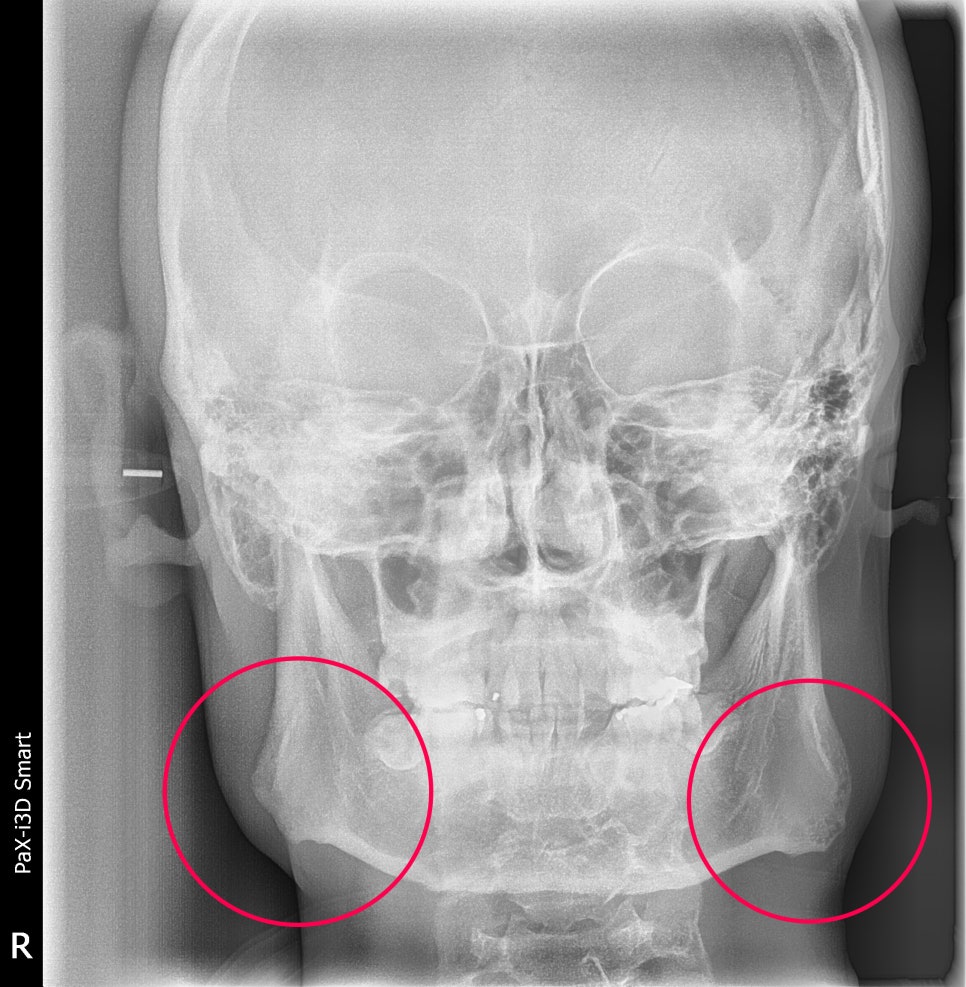

정면에서 본 모습에서도 입술의 긴장감이

같이 느껴지는 분입니다.

그리고, 구치부의 교합력이 다른 사람보다

더 높으신 분이였습니다.

아마, 식습관에서 확인을 할 수 있는데

오징어나 땅콩처럼 질기거나 딱딱한 음식을

자주 드신 분들은 엑스레이에서 볼 수 있는것 처럼

사각턱의 경향 및 하악각에서 주름이 잡힌 듯한

쭈글쭈글한 형태를 확인 할 수 있습니다.

뼈가 자라는 느낌으로 볼 수 있으며,

한번 자라난 뼈는 깎지 않는 이상에는 원래대로

되돌아가지는 않습니다.

남성미..는 느낄 수 있으나 얼굴이 커 보여지는

그런 느낌을 받을 수 있습니다.